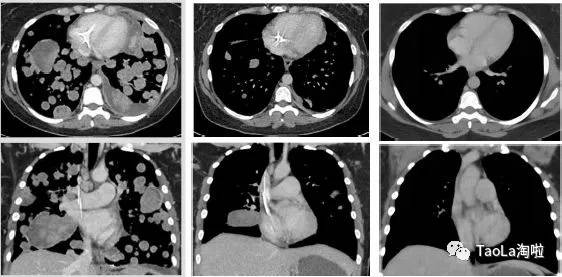

胃肠间质瘤:

55岁男性

治疗前:癌细胞几乎已经扩散到整个肠胃和腹腔

治疗后:接受了9个周期治疗后奇迹出现,肿瘤明显缩小,目前正在接受第10周期治疗。